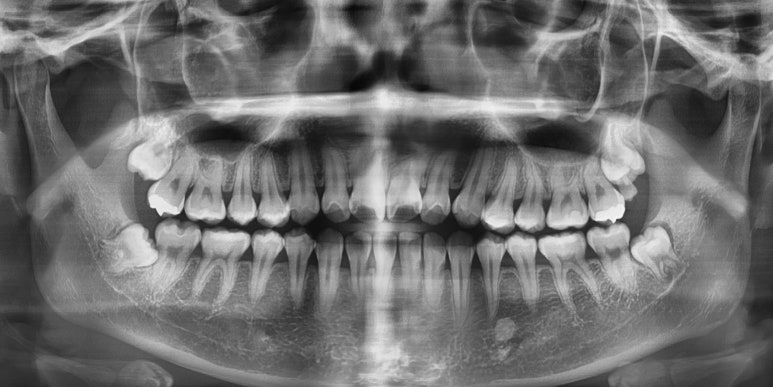

그러나 이 무료로 진행되는 국가구강검진은 눈으로 보는 검진, 즉 시진만 해당하기 때문에 치아 속에서 썩고 있는 문제나 잇몸 등의 문제는 x-ray가 필요하며 x-ray를 찍을시에는 나라에서 정해놓은 보험비가 발생합니다.

(x-ray비용은 몇천원 정도입니다)

간혹 전체 신체건강검진을 받으면서 구강검진을 받았다는 분들이 오셔도 치아x-ray를 찍지않고 검사받은 분들이 계셔서 x-ray를 찍어보면 눈으로 보이지 않았던 안에서 심하게 썩은 충치를 발견하는 경우가 있으니

x-ray를 찍어보신지 오래되셨다면 될 수 있으면 x-ray도 찍어서 확실하게 검사받는 것을 권장드립니다!

x-ray없는 치과진료는 수박겉핥기 식의 진단이 되기 쉽거든요.